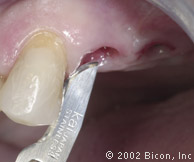

4. | 在腭侧导板的帮助下用先锋钻预备牙槽骨后的 |